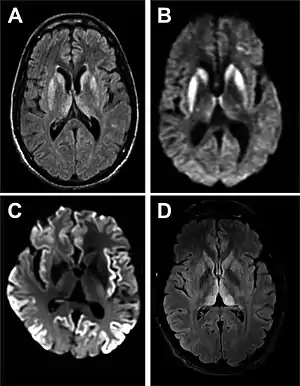

| Magnetic resonance image of sporadic CJD[3] | |

Imaging of the brain may be performed during medical evaluation, both to rule out other causes and to obtain supportive evidence for diagnosis. Imaging findings are variable in their appearance, and also variable in sensitivity and specificity.[41] While imaging plays a lesser role in diagnosis of CJD,[42] characteristic findings on brain MRI in some cases may precede onset of clinical manifestations.[43]

Brain MRI is the most useful imaging modality for changes related to CJD. Of the MRI sequences, diffuse-weighted imaging sequences are most sensitive. Characteristic findings are as follows:

- Focal or diffuse diffusion-restriction involving the cerebral cortex and/or basal ganglia. In about 24% of cases DWI shows only cortical hyperintensity; in 68%, cortical and subcortical abnormalities; and in 5%, only subcortical anomalies.[44] The most iconic and striking cortical abnormality has been called "cortical ribboning" or "cortical ribbon sign" due to hyperintensities resembling ribbons appearing in the cortex on MRI.[45] The involvement of the thalamus can be found in sCJD, is even stronger and constant in vCJD.[46]

- Varying degree of symmetric T2 hyperintense signal changes in the basal ganglia (i.e., caudate and putamen), and to a lesser extent globus pallidus and occipital cortex.[42]